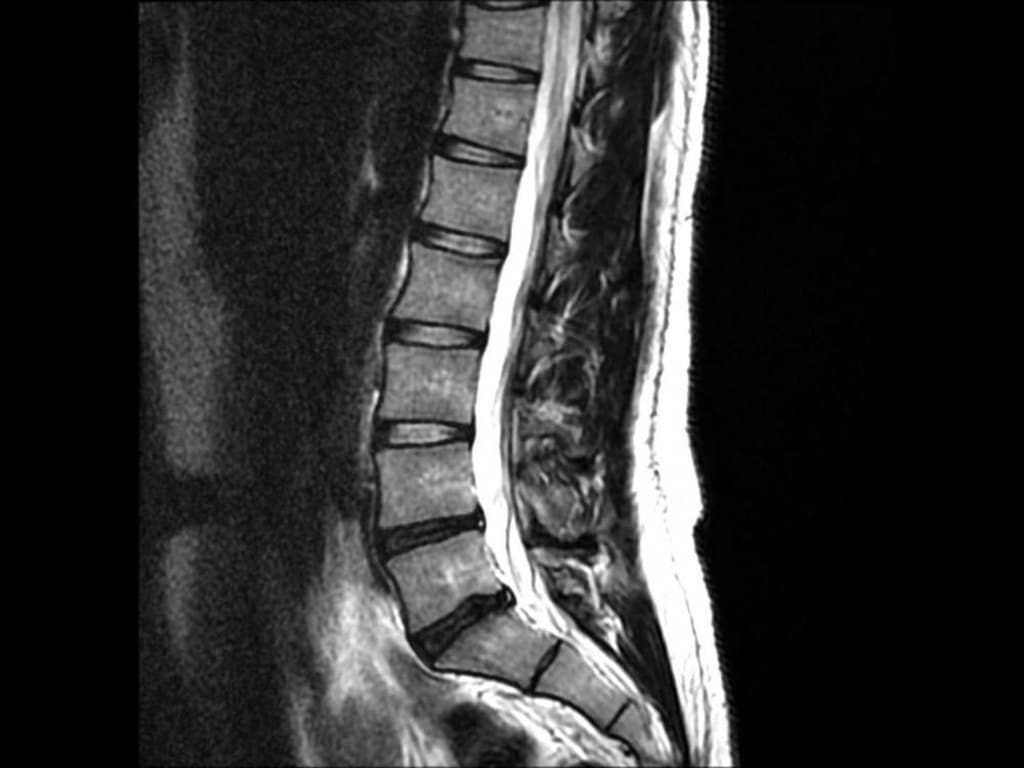

Lower back and leg pain is often mistaken for muscle tension. As a result, those affected often resort to ointments, warm compresses, or painkillers without consulting a doctor. However, sciatica can have various causes, such as a herniated disc, a bulging disc, spinal stenosis, muscle inflammation, or an injury.